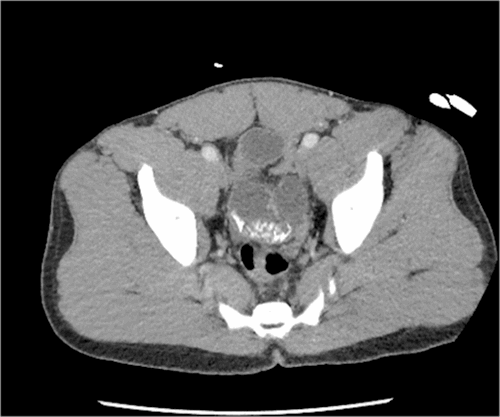

A 41-year-old previously healthy Libyan male presented with a two-day history of nausea, vomiting, and abdominal pain. He reported an inability to tolerate sips of water. He describes no changes in his diet and no strange or abnormal items being ingested before this episode. He had never experienced this type of pain or bloating before. He had a very firm, muscular abdomen with severe distention. He was diffusely tender but did not have signs of peritonitis. He was mildly tachycardic to 110 beats per minute. At this time, his laboratory evaluation showed acute kidney injury with creatinine elevation to 2.5 mg/dL and hypochloremic, hypokalemic metabolic alkalosis from repeated emesis. Given this clinical picture, a CT scan was obtained, which showed a high-grade mechanical obstruction in the distal ileum associated with a calcified density or mass (Figure 1). Additional calcified densities were identified more proximal in the small intestine located in the pelvis (Figure 2). Due to the high-grade obstruction and the calcified mass, surgical intervention was recommended. The patient was very hesitant initially but finally agreed to undergo exploratory laparotomy with possible small bowel resection.

Figure 2. Calcified Densities in Pelvis. Published with Permission